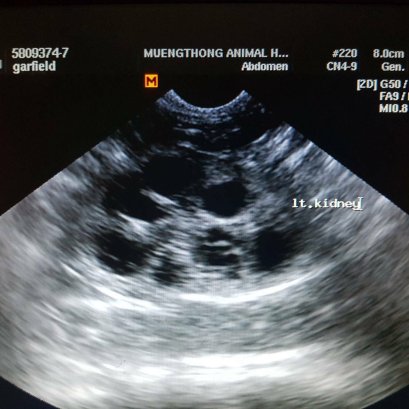

แมวผมนอนตะแคงแล้วจะเห็นก้อนปูดๆที่ท้องครับหมอ สงสัยว่าน้องจะเป็นฝี หมอคลำดูไม่มีก้อนฝีที่ผิวหนังนะคะ คลำเจอแต่ไต พบ 2 ข้างเลย มีขนาดใหญ่ เจ้าของยังสงสัยคุณหมอจึง x-ray ช่องท้องดู พบว่าไตมีขนาดใหญ่กว่าปกติ จึงต้องตรวจเลือดและ ultrasound ช่องท้องเพิ่มเติม ผลปรากฏว่า น้องเป็น ถุงน้ำในไต (Polycystic Kidney Disease)